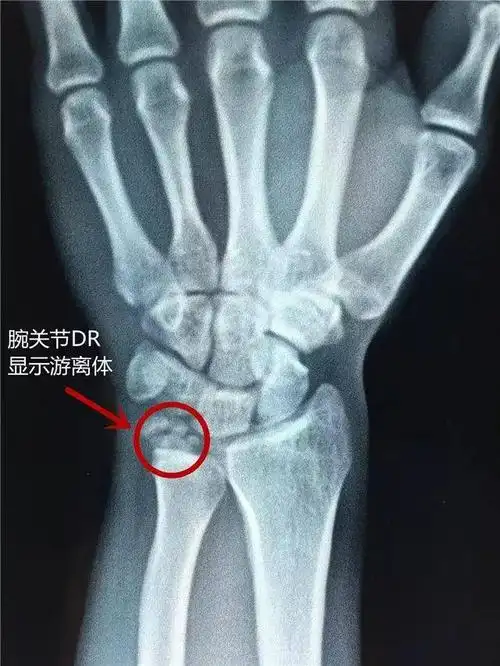

和生活,经熟人介绍他来到了郑州人民医院骨科三病区(骨关节外科)就诊